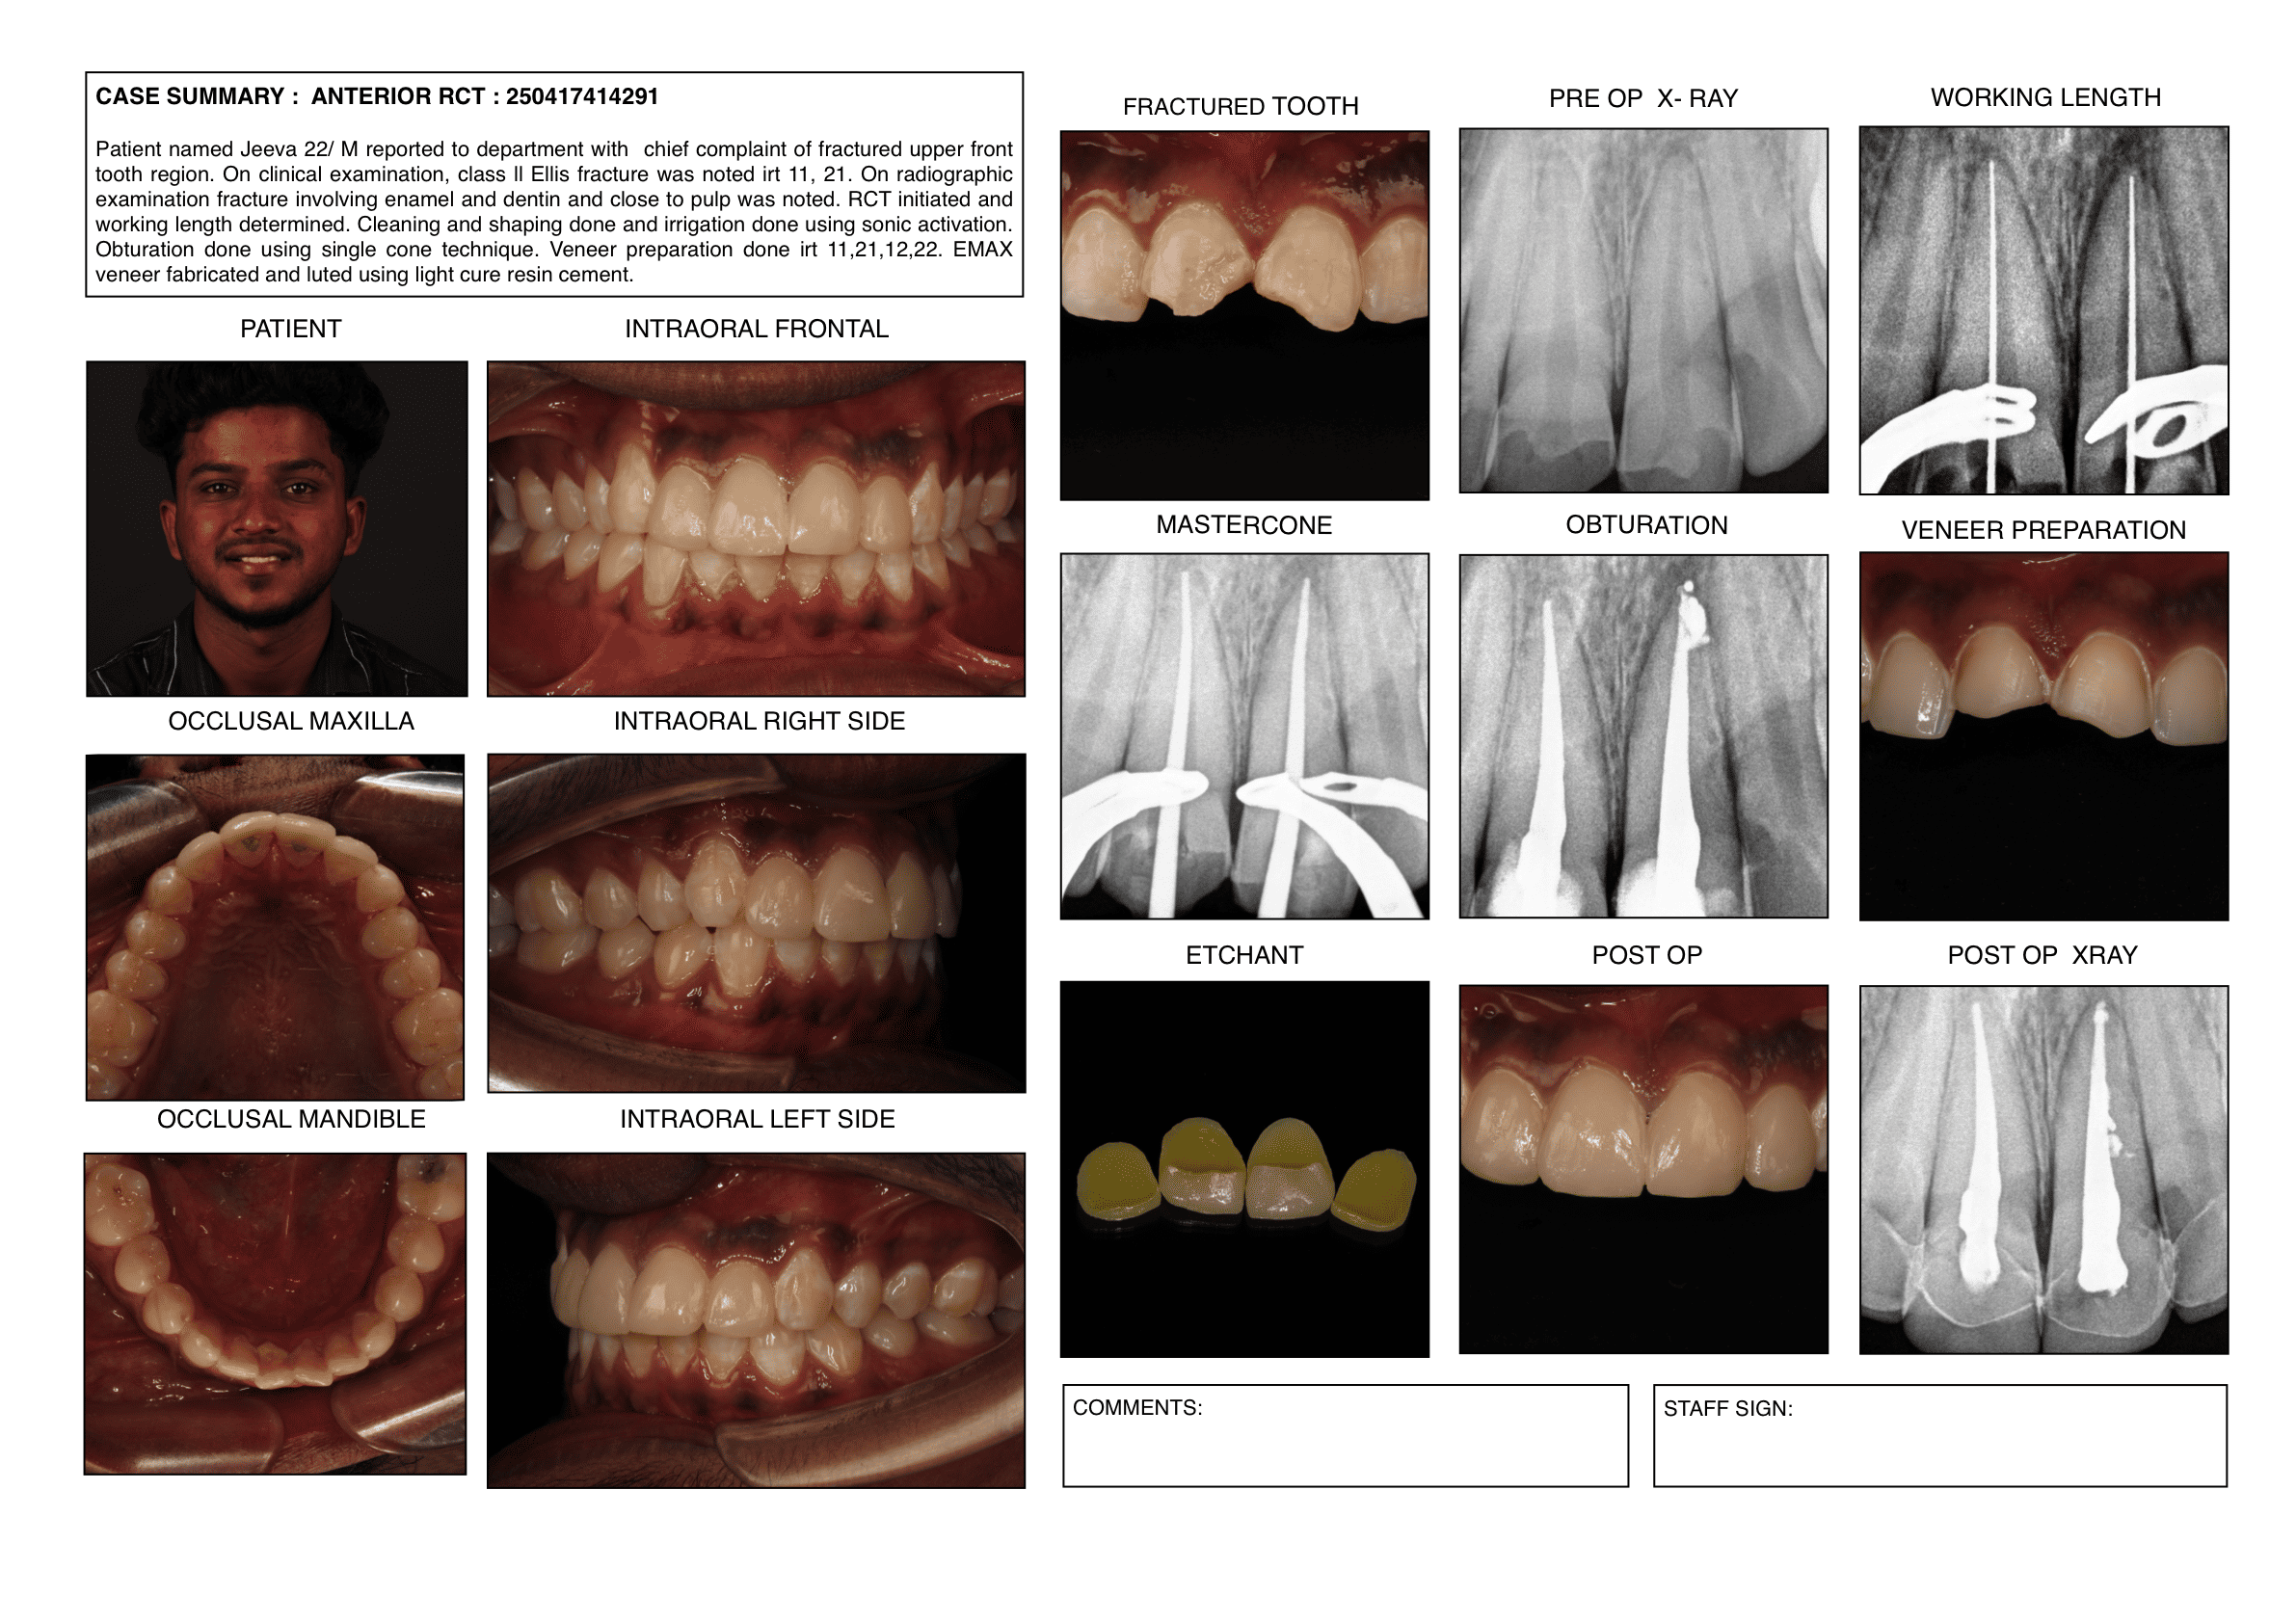

Endodontic cases